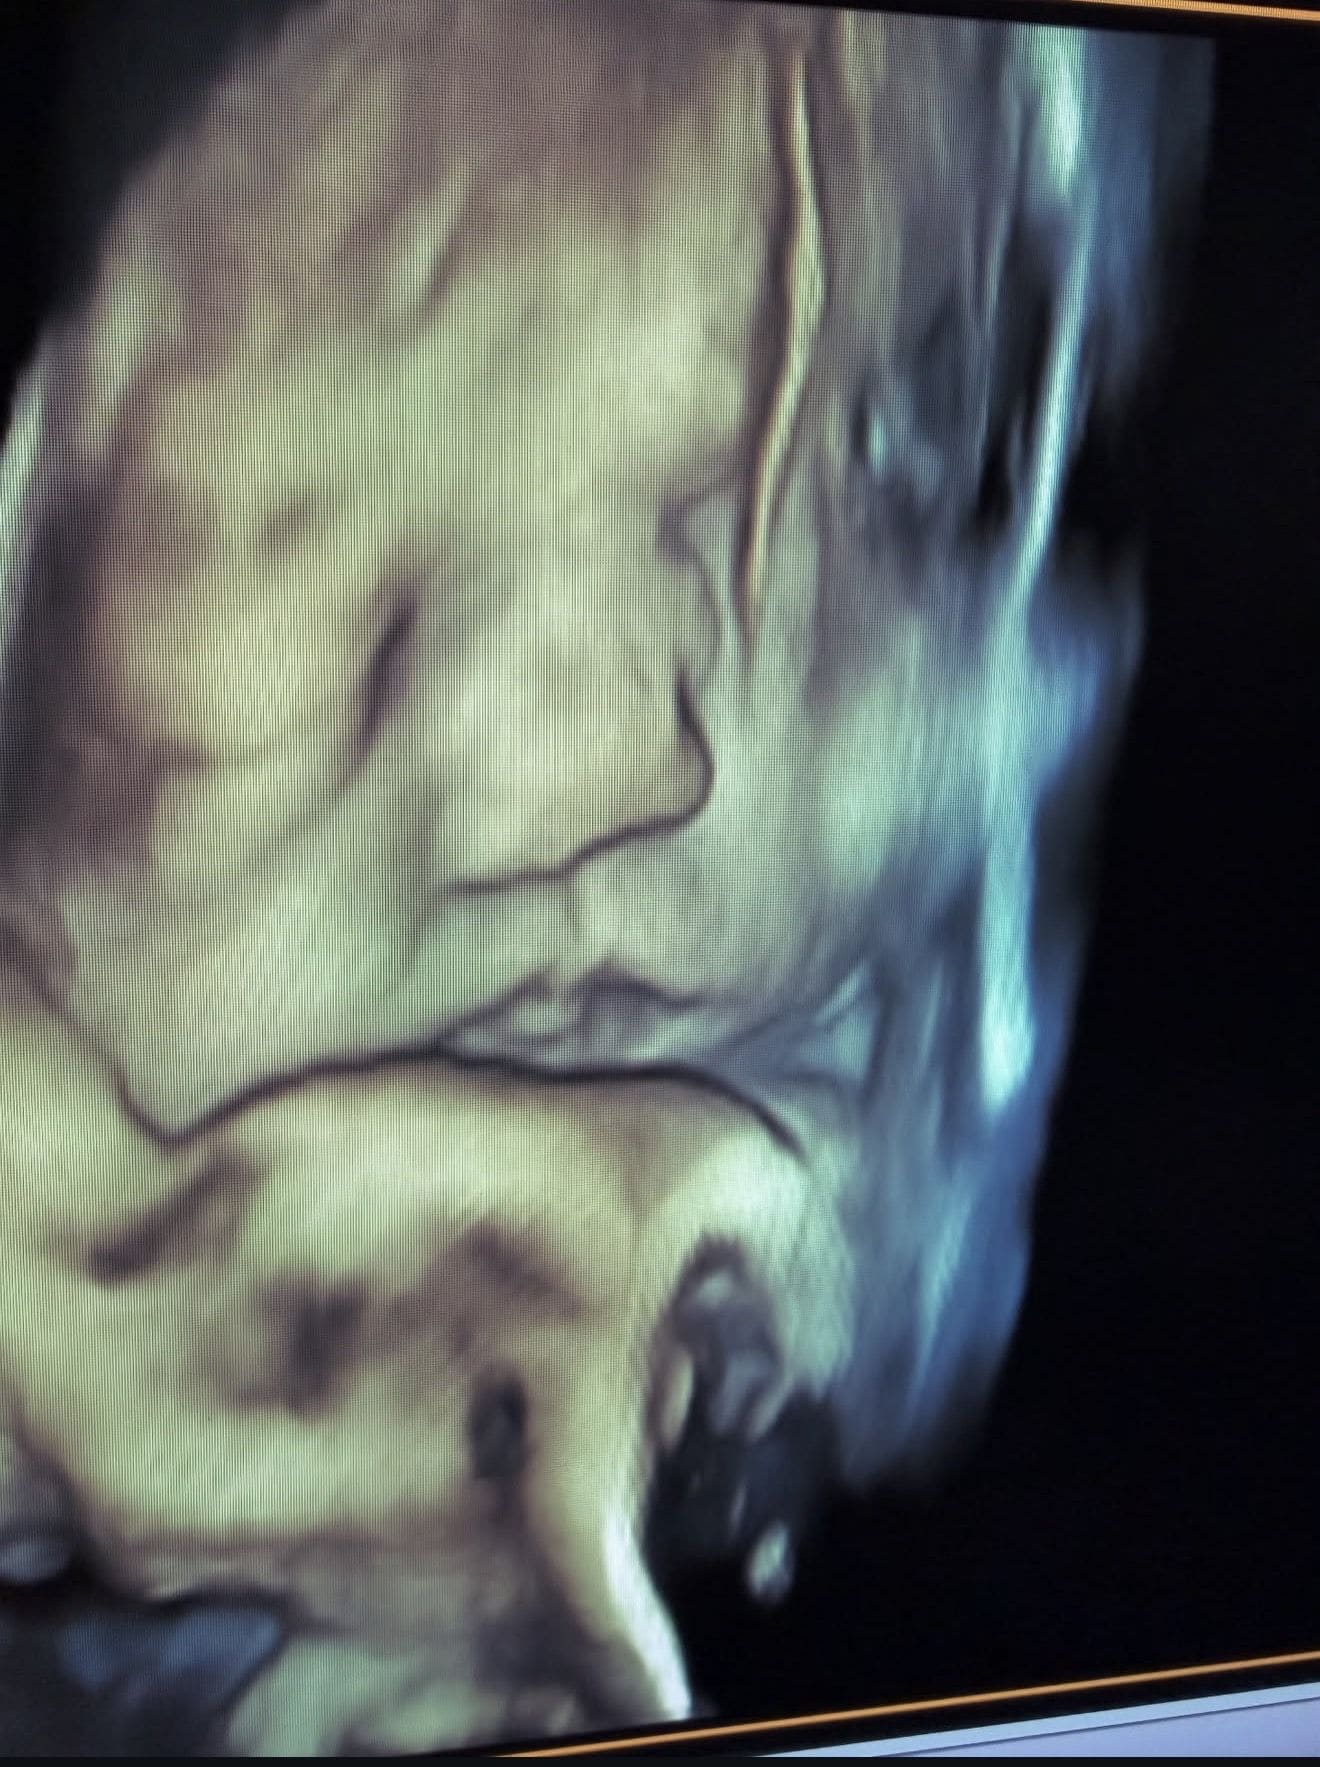

4D Ultrasound